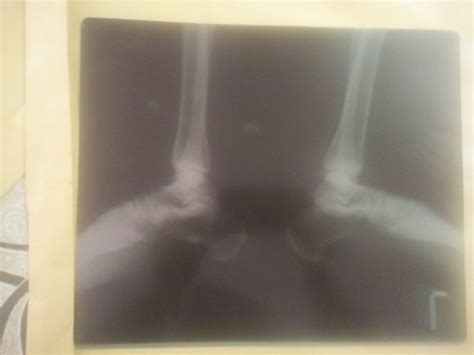

Calcaneal Spur